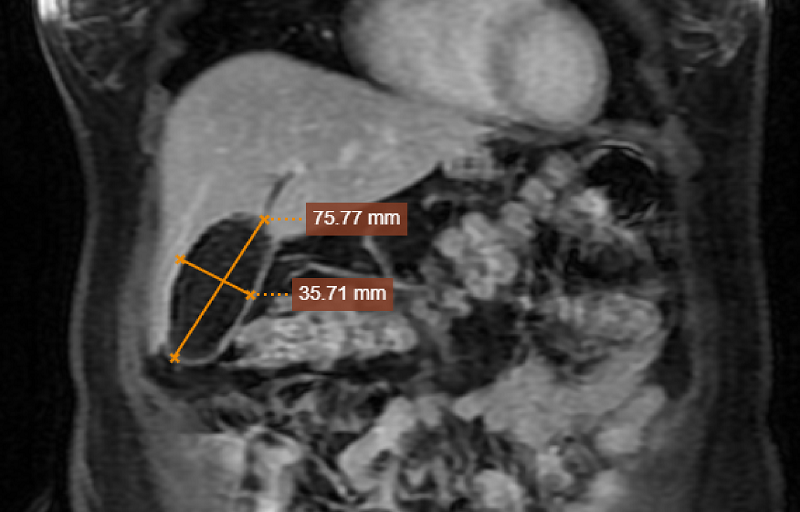

Trước hình ảnh bất thường đó, mặc dù tiếp nhận siêu âm ca bệnh trong đêm, nhưng ThS.BS Phạm Như Ánh - Khoa Chẩn đoán hình ảnh, Bệnh viện Đa khoa MEDLATEC nhanh chóng kết nối hội chẩn cùng BSCKII. Nguyễn Văn Thưởng - Trưởng Khoa Ngoại, Bệnh viện Đa khoa MEDLATEC và tư vấn bệnh nhân chụp cộng hưởng từ (MRI) gan mật có tiêm thuốc đối quang từ.

Chụp cộng hưởng từ cho thấy túi mật chứa đầy sỏi, kích thước 78x25mm |

BSCKII. Nguyễn Văn Thưởng cho biết: Chụp MRI sỏi mật có giá trị để đánh giá đường mật trong và ngoài gan giãn hay không, có sỏi túi mật hay không, đánh giá cổ túi mật có thuận lợi không, xung quanh túi mật có viêm dính không để tiên lượng cuộc mổ là thuận lợi hay khó khăn.

Kết quả chụp MRI của bệnh nhân có sỏi túi mật nhiều viên đúc đầy túi mật, không thấy dấu hiệu viêm túi mật. Ngay sau đó, bệnh nhân được BS Thưởng cùng ê-kíp y bác sĩ chuyên khoa Ngoại thực hiện mổ cắt túi mật chủ động qua nội soi.

Chuyên gia lưu ý, người Việt Nam có đặc điểm cơ địa người nhỏ nên đại đa số chỉ cần siêu âm là đủ điều kiện để chẩn đoán có sỏi túi mật hay không. Tuy nhiên, trường hợp bệnh nhân người Brazil có thể trạng béo phì (BMI=34,4 kg/m2), bị viêm túi mật mạn tính, toàn bộ túi mật lấp đầy sỏi, vì vậy, bác sĩ phải có nhiều kinh nghiệm mới đọc được kết quả đây là sỏi túi mật.

Bày tỏ sự ngưỡng mộ đánh giá chính xác ca bệnh, chuyên gia chia sẻ: “Với 33 năm kinh nghiệm thực hiện siêu âm, tôi vô cùng ngưỡng mộ bác sĩ siêu âm trường hợp này. Thông thường để xác định có sỏi túi mật chỉ cần siêu âm là đủ, nhưng trước khi có chỉ định có mổ, bác sĩ chỉ định bệnh nhân chụp MRI là hoàn toàn phù hợp để có "bức tranh" tổng thể của sỏi túi mật”.

Chung đánh giá với chuyên gia Trần Công Hoan về ca bệnh này, PGS.TS.BSCC Nguyễn Quốc Dũng - Phó Chủ tịch Hội Điện quang và Y học hạt nhân Việt Nam, Phó Chủ tịch Hội đồng Khoa học công nghệ và đào tạo MEDLATEC GROUP, Giám đốc Chuyên môn Trung tâm Chẩn đoán hình ảnh MEDLATEC với hơn 40 năm kinh nghiệm một lần nữa nhấn mạnh: “Bệnh nhân này có thể trạng béo phì, triệu chứng không rầm rộ, siêu âm dễ bỏ sót vì không nhìn thấy dịch mật, nên không thấy cấu trúc giải phẫu túi mật, hình ảnh túi mật không thông thường, không có dịch mật, nhưng bác sĩ siêu âm đã chẩn đoán chính xác để đi đến điều trị kịp thời, an toàn cho người bệnh”.